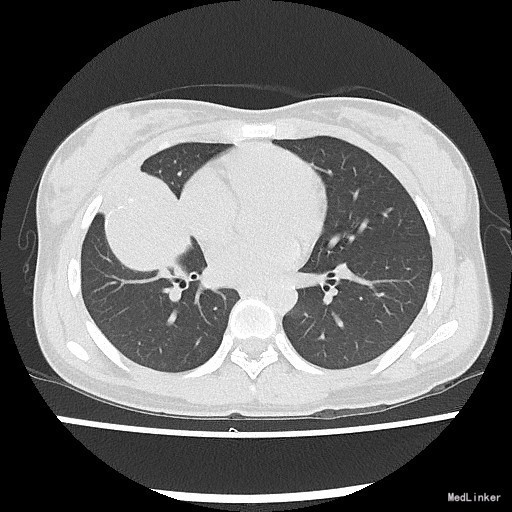

患者:女,18岁 主诉:体检发现右肺结节1月 病史:者1月前体检发现右肺结节1月,不伴咳嗽、胸闷气促、呼吸困难、胸痛、咯血,当时患者因高考未能及时治疗。近期体重无明显改变。

查体:一般情况良好,心肺腹均未见异常。 胸部X片示:右肺结节,性质待定,建议进一步检查。

诊断:肺部肿物(查因?) 治疗:住院后完善相关检查,胸部螺旋CT提示:右肺中叶囊实性肿物,恶性肿瘤待排。排除手术禁忌症,遂于全麻下行胸腔镜辅助下右中下肺叶切除,淋巴结清扫术。术后病理示:粘液表皮样癌。 (右中叶开口肿物)纤维结缔组织内见较多表皮样细胞、粘液细胞及中间细胞,部分形成腺腔样结构,结合免疫组化及特殊染色,符合粘液表皮样癌。 免疫组化结果(②):CEA(+),CK14(灶性+),TTF-1(-),Vimentin(-),CK7(+),Ki-67(2%+),CK5/6(+),P63(+)。 特殊染色结果:PAS(+),d-PAS(+),粘液(+)。